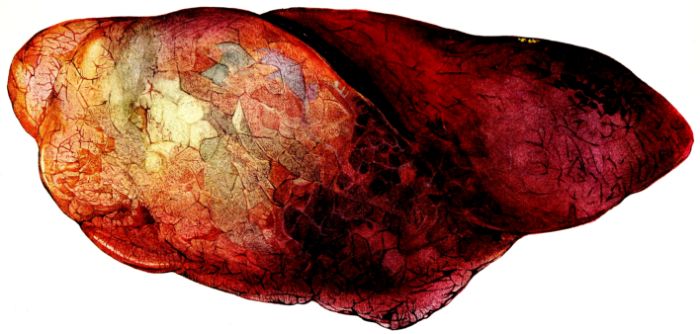

FIG. XIII. AUTOPSY NO. 96. RIGHT LUNG. A WATER COLOR DRAWING OF A GROSS LUNG IN THE ACUTE STAGE. NOTE THE SIZE OF THE LUNG, THE HEMORRHAGES ON THE PLEURAL SURFACE, AND THE BLUE AREAS OF CONSOLIDATION.

FIG. XIV. AUTOPSY NO. 96. LEFT LUNG. NOTE ITS SIZE AND THE PATCHY CONSOLIDATION.

19The lungs are extremely voluminous (12, 17) due in part to an accumulation of liquid within them. This finds its way into the trachea and completely fills the latter structure with blood-stained, syrupy fluid, with purulent material, or with a mixture of these (2, 90, 107, 157, 162). At first the pleural surface is smooth and often quite even, but on closer inspection, a minute granulation is suggested. In many cases even close examination does not allow the conclusion that an exudation of anything but serum has occurred through this membrane, except in localized foci. These foci more frequently involve the interlobar pleura and that of the lower lobes (112, 143). The volume of the lungs, often great enough to obliterate the pericardial area, is one of the two most characteristic features of the external examination. The other feature is their color. Small, bright red hemorrhages may occur anywhere. The larger patches are the most striking. Violet, purple, or dark brown areas, irregular in shape and distribution, are more frequently found on that portion of the pleura over the lower two-thirds of the lung. Between the deeply colored zones, there are pale pink areas which involve the lowermost edge to the least degree, the anterior margin somewhat more, and the apex of the lung most of all. The darker portions just referred to may project above the surface and may be circumscribed, resembling huge, fresh hemorrhagic infarcts (41, 108). The alveolar walls are not seen through the pleural surfaces in these darker zones. The pale pink areas, usually at the level of the more intensely colored zones, may be elevated and the dilated air sacs are distinctly made out through the pleura (Fig. XIII). At the hilum, the lymph glands are large and soft. When cut, fluid escapes and is often blood-stained. The cross section may present a distinct, diffuse, hemorrhagic appearance (162). At the hilus, too, the lymphatics, distended here and there over the surface of the pleura, are most affected. The congested bronchial mucous membrane and the exudate in these structures has been described.

After removal, the lung retains its shape, but is more flaccid than the consolidated lung of lobar pneumonia. It cuts with very little resistance and immediately a large amount of a syrupy, pink fluid escapes and obscures the entire area. With the fluid scraped away, the variations in the consistency of the lung become visible. The pale areas around the borders and chiefly at the apex in which the air sacs are discernible with the naked eye, sink slightly below the remainder of the surface, and the pleural edge inverts. The individual lobules of the lung in these areas are more conspicuous than normal, because the interstitial tissue bearing the lymphatics and vessels, as well as that around the bronchi and larger blood vessels, does not lose its edematous appearance as quickly as the alveoli (40, 92, 110, 164), and, consequently, these grey lines and points stand up somewhat more prominently.[6] In contrast with the paler areas which are prone to slight collapse, the remainder of the cross section retains its more smooth and even surface. The alveolar walls are not distinctly made out, but the terminal bronchioles often make themselves evident by the nature of the material which is within and by their distinct dilatation (1, 67, 110, 149, 162). The more firm areas stand out, too, on account of their difference in color. The scheme is not unlike that seen on the pleural surface, and while dark, almost black, infarct-like areas occur on the cut surface, the solid areas are more likely to be translucent, dull, light red, brown or even grey. They have a surface similar to a very fresh, tuberculous, gelatinous pneumonia, but the color differs from the cloudy grey of the latter on account of the admixture of blood in the exudate and the great congestion of the vessels (Fig. XIV).

The well developed post-mortem muscular rigidity, the lividity of the dependent parts, of the face with its mucous membranes, and often of the trunk, the jaundice variable in extent, the crusts of blood on the nares and mouth, and the splanchnic dilatation are features which prepare for the gross picture presented by the thoracic organs. The increased moisture within the pleural cavities associated with the even, translucent pleural surface, whose dilated lymphatics become more and more prominent towards the hilum, the large succulent lymph glands, and the exudate in the bronchial tree, are all striking, but more characteristic of the gross picture, is the great increase in volume of the lung itself, mottled 20with brilliant colors. The lung, too, is very wet and on section, after the syrupy, blood-stained fluid escapes from the less definitely consolidated zones, the latter appear, not as the usual granular, firm areas of hepatization, but have more the consistency of a gel, and also its translucence. Characteristic of this disease as these changes may be, the specificity of the fundamental lesion in the respiratory tract, becomes more emphatic after study of its histology (92, 162).

The lung remains increased in volume and its surface is mottled with vivid colors. Often these are an indication of deeper parenchymatous change. The pale pink zones, through the pleural surface of which distended alveoli are discernible, are still prominent in the upper lobe, around the margins, and on the anterior surface of the lung. The darker purple, slightly elevated, often circumscribed, infarct-like areas (25, 34, 108) may occur anywhere, but are more frequent in the lower lobes. Small, maroon, slightly depressed areas of atelectasis may also involve the borders of the lung, usually the posterior borders; or they may occur between larger and more elevated areas on either lobe. Besides the purple, firm, projecting foci, paler pink or grey nodules of similar consistence may be present and show no structure when viewed through the pleura. The distribution of the different types of change is variable, and, aside from the fact that they involve the middle and lower lobes more frequently than the upper, no general statement is possible. In a few instances, one lobe, almost always the lower, may be more voluminous than the others, and although its pleura often suggests lobular involvement, the masses tend to be confluent and suggest a pseudolobar change. Sometimes, though rarely, this approaches a true lobar type of consolidation. (Compare Figs. XIII and XXVII.) Occasionally, the changes in the lung, except its increase in size, are obscured by pleural exudate which may form a thick, buttery, rather sticky mass on the surface (12, 19, 157) (Fig. XXXVII). Such pleural exudates are rare, and likewise it is uncommon to find so little pleural granulation as in the previous group. The roughening, as a rule, is not uniform, but is more prominent over the lower lobes and in the interlobar spaces than elsewhere. It may occur when there is no definite increase in the fluid content of the pleural sac.